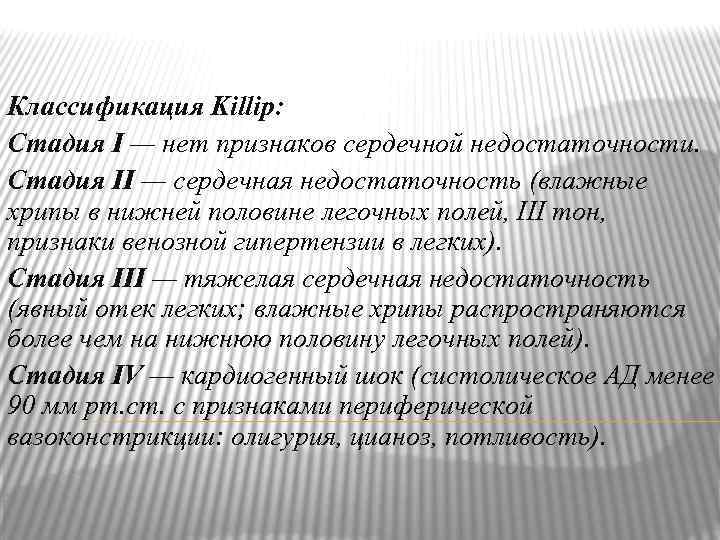

Классификация Killip: Стадия I — нет признаков сердечной недостаточности. Стадия II — сердечная недостаточность (влажные хрипы в нижней половине легочных полей, III тон, признаки венозной гипертензии в легких). Стадия III — тяжелая сердечная недостаточность (явный отек легких; влажные хрипы распространяются более чем на нижнюю половину легочных полей). Стадия IV — кардиогенный шок (систолическое АД менее 90 мм рт. с признаками периферической вазоконстрикции: олигурия, цианоз, потливость).

Классификация Killip: Стадия I — нет признаков сердечной недостаточности. Стадия II — сердечная недостаточность (влажные хрипы в нижней половине легочных полей, III тон, признаки венозной гипертензии в легких). Стадия III — тяжелая сердечная недостаточность (явный отек легких; влажные хрипы распространяются более чем на нижнюю половину легочных полей). Стадия IV — кардиогенный шок (систолическое АД менее 90 мм рт. с признаками периферической вазоконстрикции: олигурия, цианоз, потливость).